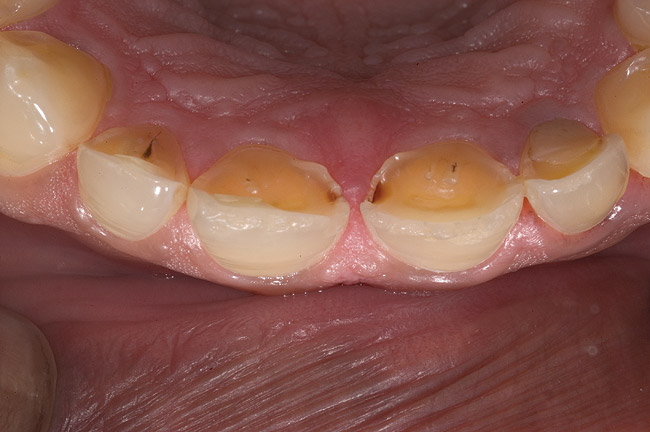

Figure 6  1:1 view demonstrating severe loss of tooth structure due to palatal erosion.

Figure 6